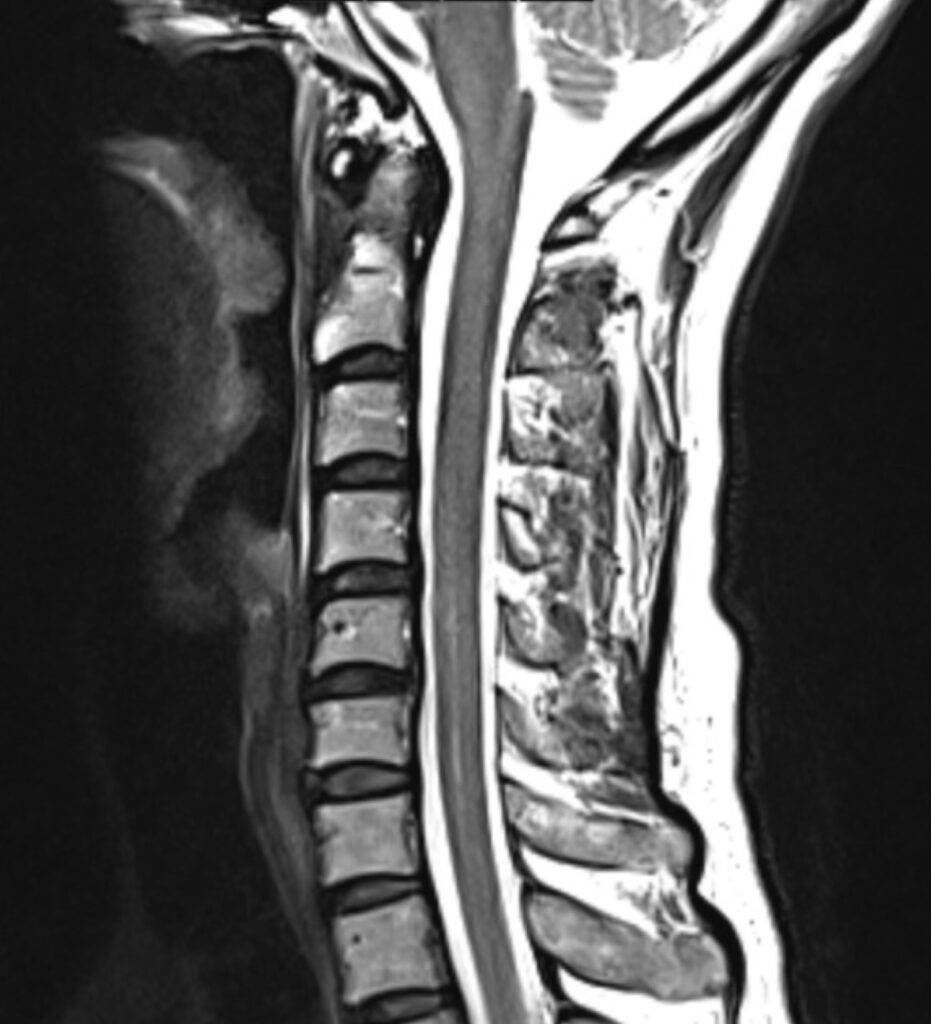

Die Magnetresonanztomographie der Halbwirbelsäule, kurz MRT HWS genannt, ist ein bildgebendes Diagnoseverfahren. In einer MRT HWS ist es möglich, den Bereich der Halswirbelsäule mit allen anatomischen Strukturen bildlich darzustellen. Besonders im Falle eines Verdachts auf Bandscheibenvorfall im Bereich der HWS ist eine Magnetresonanztomographie die bevorzugte Diagnosemethode.

Bei einer MRT der Halswirbelsäule wird der Nackenbereich abgebildet. Die unterschiedlichen anatomischen Strukturen können präzise dargestellt werden und dienen der Beurteilung von Erkrankungen der Halswirbelsäule.

Was sieht man alles auf einer MRT HWS?

| Wirbelkörper | Einzelne Wirbelkörper, Form und Struktur |

| Bandscheiben | Bandscheiben zwischen den Wirbeln |

| Rückenmark und Nervenwurzel | Gesamter Wirbelkanal |

| Weichteile | Muskeln, Bänder, Lymphknoten |